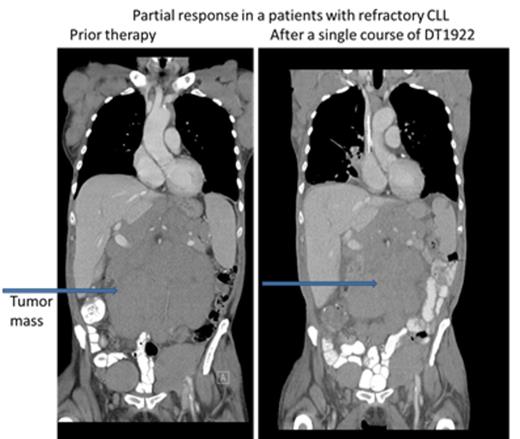

We conducted a phase 1 study to assess safety, to determine the maximum tolerated dose (MTD) and to evaluate preliminary efficacy in patients with chemotherapy refractory B cell leukemia or lymphoma expressing CD19 and/or CD22. DT2219 was administered in a single course intravenously over 4 hours (1-2 hours for subsequent doses) every other day for 4 total doses. The starting dose was 0.5 µg/kg/dose (2.0 ug/kg/course) (1/1000th of the MTD in rabbits). The dose was escalated by accelerated design until dose limited toxicity (DLT) was observed. Twenty-two patients were enrolled, with a median age of 55 years (range, 34-78). Five patients had pre-B acute lymphoblastic leukemia (4 refractory, 1 with extra-medullary disease, 1 had chronic lymphocytic leukemia (CLL) and 7 had non-Hodgkin lymphoma). All were chemo-refractory with a median of 4 prior therapies. All patients had biopsy-confirmed tumor expression of CD19 and/or CD22. The first 9 patients were treated at doses ranging from 0.5 ug/kg/dose to 20 ug/kg/dose. No drug was detectable in those patients and they experienced no DLT or clinical responses. DT2219 was detectable in the serum at doses ≥40 µg/kg/dose (N=13). Dose levels were 40 µg/kg/day N=5; 60 µg/kg/day N=5; 80 µg/kg/day N=3. The area under the curve (AUC ) range was 1,104 -1,346 and the half-life ranged from 54-84 minutes. After a single course of DT2219 we observed partial remission in a 77 year old patient with rituximab/chemotherapy-refractory CLL (dose level 40 µg/kg). The 40% reduction in the abdominal tumor mass is shown in Figure 1. This patient did not experience any DLT. A second partial remission was observed in 53 year old patient with relapsed marginal zone lymphoma (dose level 60 µg/kg) who experienced a DLT of capillary leak syndrome. After regulatory approval, that patient received a second treatment course 8 weeks later at a reduced dose of 40 µg/kg which resulted in a complete remission (Figure 2). Both patients are alive and in remission at 6 and 4 months, respectively, after therapy. Adverse events were observed in all patients who received ≥40 µg/kg. The most common was grade 1-2 capillary leak syndrome, grade 1-2 hematologic toxicity, elevated liver function tests and fatigue. Two patients experienced DLTs: at the 40 µg/kg dose (grade 3 lower extremity weakness) and 60 µg/kg dose ( grade 4 neutropenia and grade 3 capillary leak). All adverse reactions resolved completely within one week. Immunogenicity and formation of neutralizing antibodies is a major barrier in development of DT-based immunotoxins. Remarkably, none of the 8 patients with B-cell lymphoma/CLL who had received rituximab within weeks preceding therapy with DT2219 had detectable neutralizing antibody. These patients had no detectable B cells at the time of study drug administration. This suggests that rituximab pre-treatment may prevent the development of neutralizing antibodies and allow for repetitive dosing. In conclusion, we have demonstrated promising clinical efficacy of the novel immunotoxin DT2219 in refractory B cell lymphoid malignancies. We determined that the biologically active dose of DT2219 is between 40-80 µg/kg and that repetitive dosing is feasible in patients pre-treated with rituximab. Phase 2 trial is in development.

CT images of 77 year old patient with refractory CLL after a single course of DT1922 at dose level 40 µg/kg.